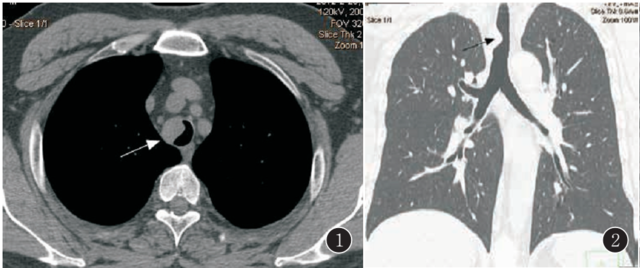

气管Rosa-iDorfman病

气管Rosa-iDorfman病气管Rosa-iDorfman病气管Rosa-iDorfman病气管Rosa-iDorfman病气管Rosa-iDorfman病气管Rosa-iDorfman病气管Rosa-iDorfman病